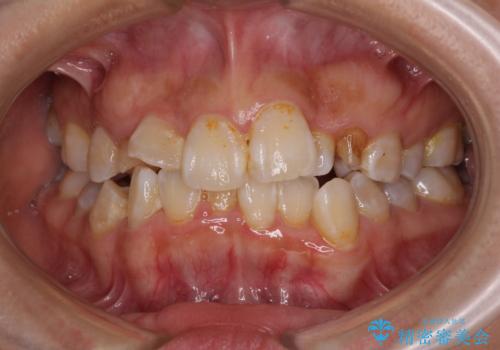

前歯綺麗にしたい。

担当医 青山卓弘